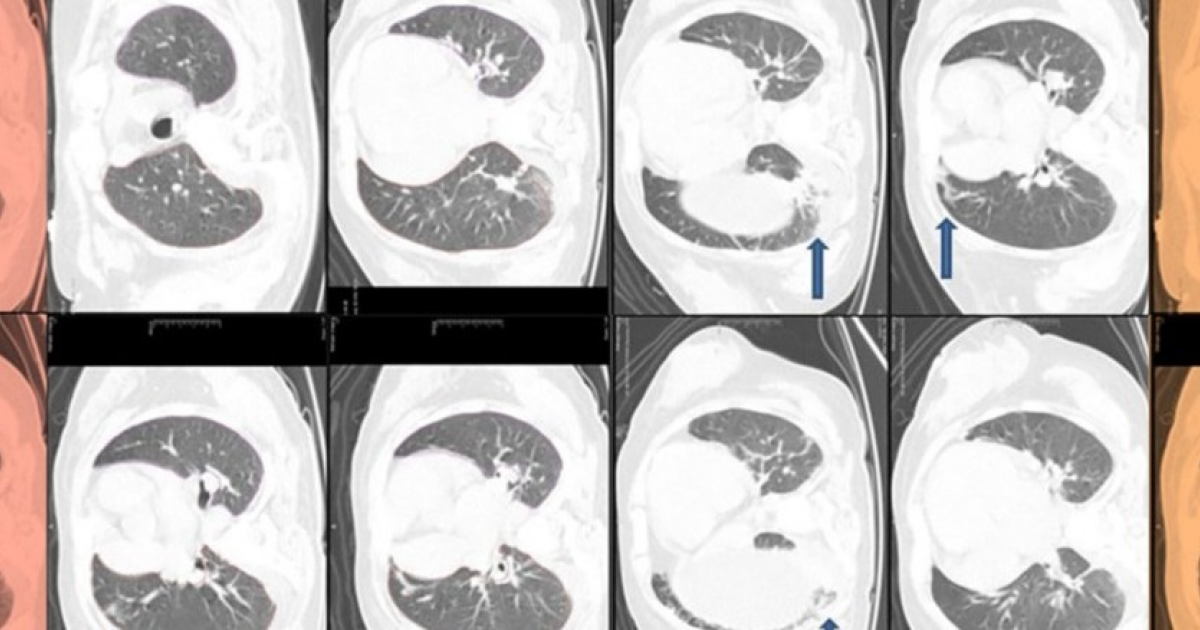

Слабость и повышенная утомляемость оказались проявлением синдрома коротких теломер.

Слабость и повышенная утомляемость оказались проявлением синдрома коротких теломер. Слабость и повышенная утомляемость оказались проявлением синдрома коротких теломер